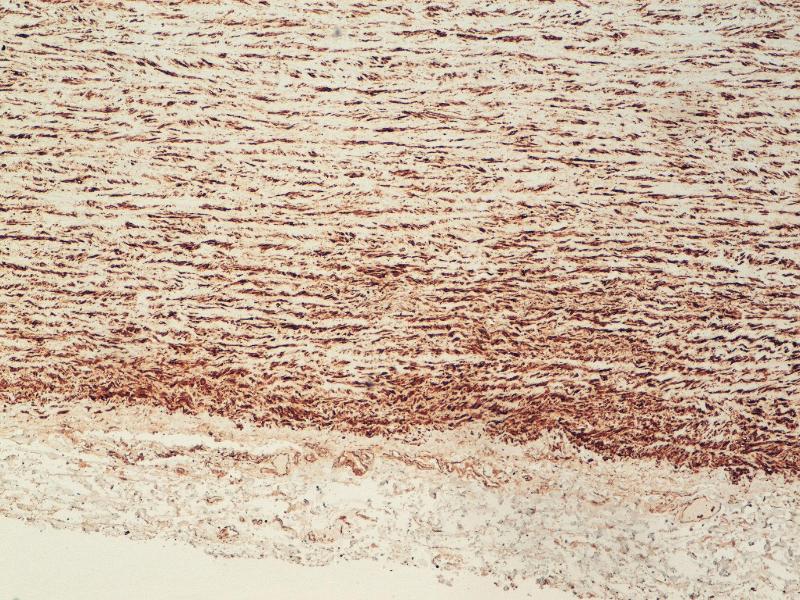

- The antibody is specific to the 100 kD a-actinin polypeptide and reacts with human and chicken cells.

- No reactivity with paraffin sections. Working dilution in western blotting is at least 1:1000

- alpha Actinin (ACTN) (alpha-Actinin Skeletal Muscle (ACTN))

- Monoclonal Antibody to Human Cytoskeletal Polypeptides